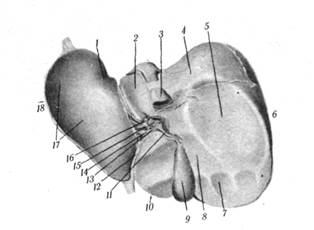

Печень (hepar) (рис.1.2) у человека является самой крупной железой. Она составляет 1/20 массы ново рожденного и около 1/50 массы тела взрослого (1,5 — 2 кг), имеет красно-бурый цвет и довольно мягкую консистенцию.

Печень расположена в брюшной полости непосредственно под диафрагмой. Большая ее часть (3/5) лежит справа. В печени, по внешнему виду напоминающей неправильную шляпку гриба, различают диафрагмальную (верхнюю) и внутренностную (нижнюю) поверхности, разделенные нижним краем (рис.1.2).

Внутренностная поверхность печени (faciesvisceralis) (рис.1.2) слегка вогнутая, со следами вдавления соседних органов. Здесь имеются две продольные (правая и левая) и одна поперечная борозды. Правая продольная борозда представлена ямкой желчного пузыря (fossavesiceaefellae), продолжением этой борозды кзади от поперечной борозды служит упомянутая борозда полой вены. Левая продольная борозда (вернее щель) является ложем двух рудиментарных образований: круглой связки печени (облитерированной пупочной вены), залегающей в переднем отделе щели (fissuratig. teretis), и венозной связки (обли-терированного венозного протока), залегающего в заднем отделе щели (fissuralig. venosi).

Рис. 1.2. Печень (вид снизу):

/ — пищеводное вдавление; 2 — хвостатая доля; 3— нижняя полая вена; 4—оголенное поле; 5—почечное вдавление; 6 — правая доля печени; 7 — ободочно-кишечное вдавление; 8 — двенадцатиперстно-кишечное вдавление; 9—желчный пузырь; 10 — квадратная доля печени; 11 — пузырный проток; 12 — круглая связка печени; 13 — общий желчный проток; 14 — общий печеночный проток; 15— воротная вена; 16 — печеночная артерия; 17 — желудочное вдавление; 18 — левая доля печени.

Поперечная борозда, или ворота печени (portahepatis), соединяет две предыдущие борозды и служит местом прохождения сосудов и нервов печени. Борозды делят внутренностную поверхность печени на четыре доли: правую (lobushepatisdexter), лежащую справа от правой продольной борозды; левую (lobushepatissinister), расположенную слева от левой продольной борозды; квадратную (lobusquadratus), ограниченную сзади воротами печени, а с боков правой и левой продольными бороздами, и хвостатую (lobuscaudatus), которая находится также между правой и левой продольными бороздами, но кзади от ворот печени.

По своему строению печень сложная сетчато-трубчатая железа, паренхиматозные элементы которой выделяют желчь. Желчь выходит из ворот печени через правый и левый печеночные протоки (ductushepatisdexteretsinister). Вскоре после выхода оба протока объединяются в общий печеночный проток (ductushepaticuscommunis) (длиной около 4—5 см), который, следуя каудально, сливается с пузырным протоком, образуя общий желчный проток (ductuscholedochus) около 12 см длиной (рис.1.2). Общий желчный проток идет книзу между листками печеночно-двенадцатиперстной связки и открывается, как было отмечено выше, вместе с главным протоком поджелудочной железы на слизистой двенадцатиперстной кишки.

Желчный пузырь (vesicafellea) (рис.1.2) возникает в раннем эмбриогенезе как мешковидное выпячивание печеночного дивертикула. У взрослого человека желчный пузырь, имеющий вид вытянутой колбы с различной емкостью (25—70 см3), расположен в переднем отрезке правой продольной борозды (ямка желчного пузыря). В нем различают дно, тело и шейку, которая постепенно переходит в пузырный проток (ductuscysticus). Стенка желчного пузыря состоит из: слизистой оболочки с подслизистой основой; слабо развитой мышечной с преимущественно круговым направлением пучков и серозной с незначительно выраженной подсерозной основой. Слизистая оболочка дна и тела имеет своеобразные складки, придающие ей вид шагреневой кожи, а в шейке и в пузырном протоке складки слизистой обычно имеют спиральный ход (спиральная складка). В печеночных и общем желчных протоках слизистая гладкая. Серозная оболочка покрывает большую часть желчного пузыря, остальная часть срастается с фиброзной капсулой печени посредством рыхлой клетчатки. Печеночные и общий желчные протоки расположены в толще печеночно-двенадцатиперстнокишечной связки.